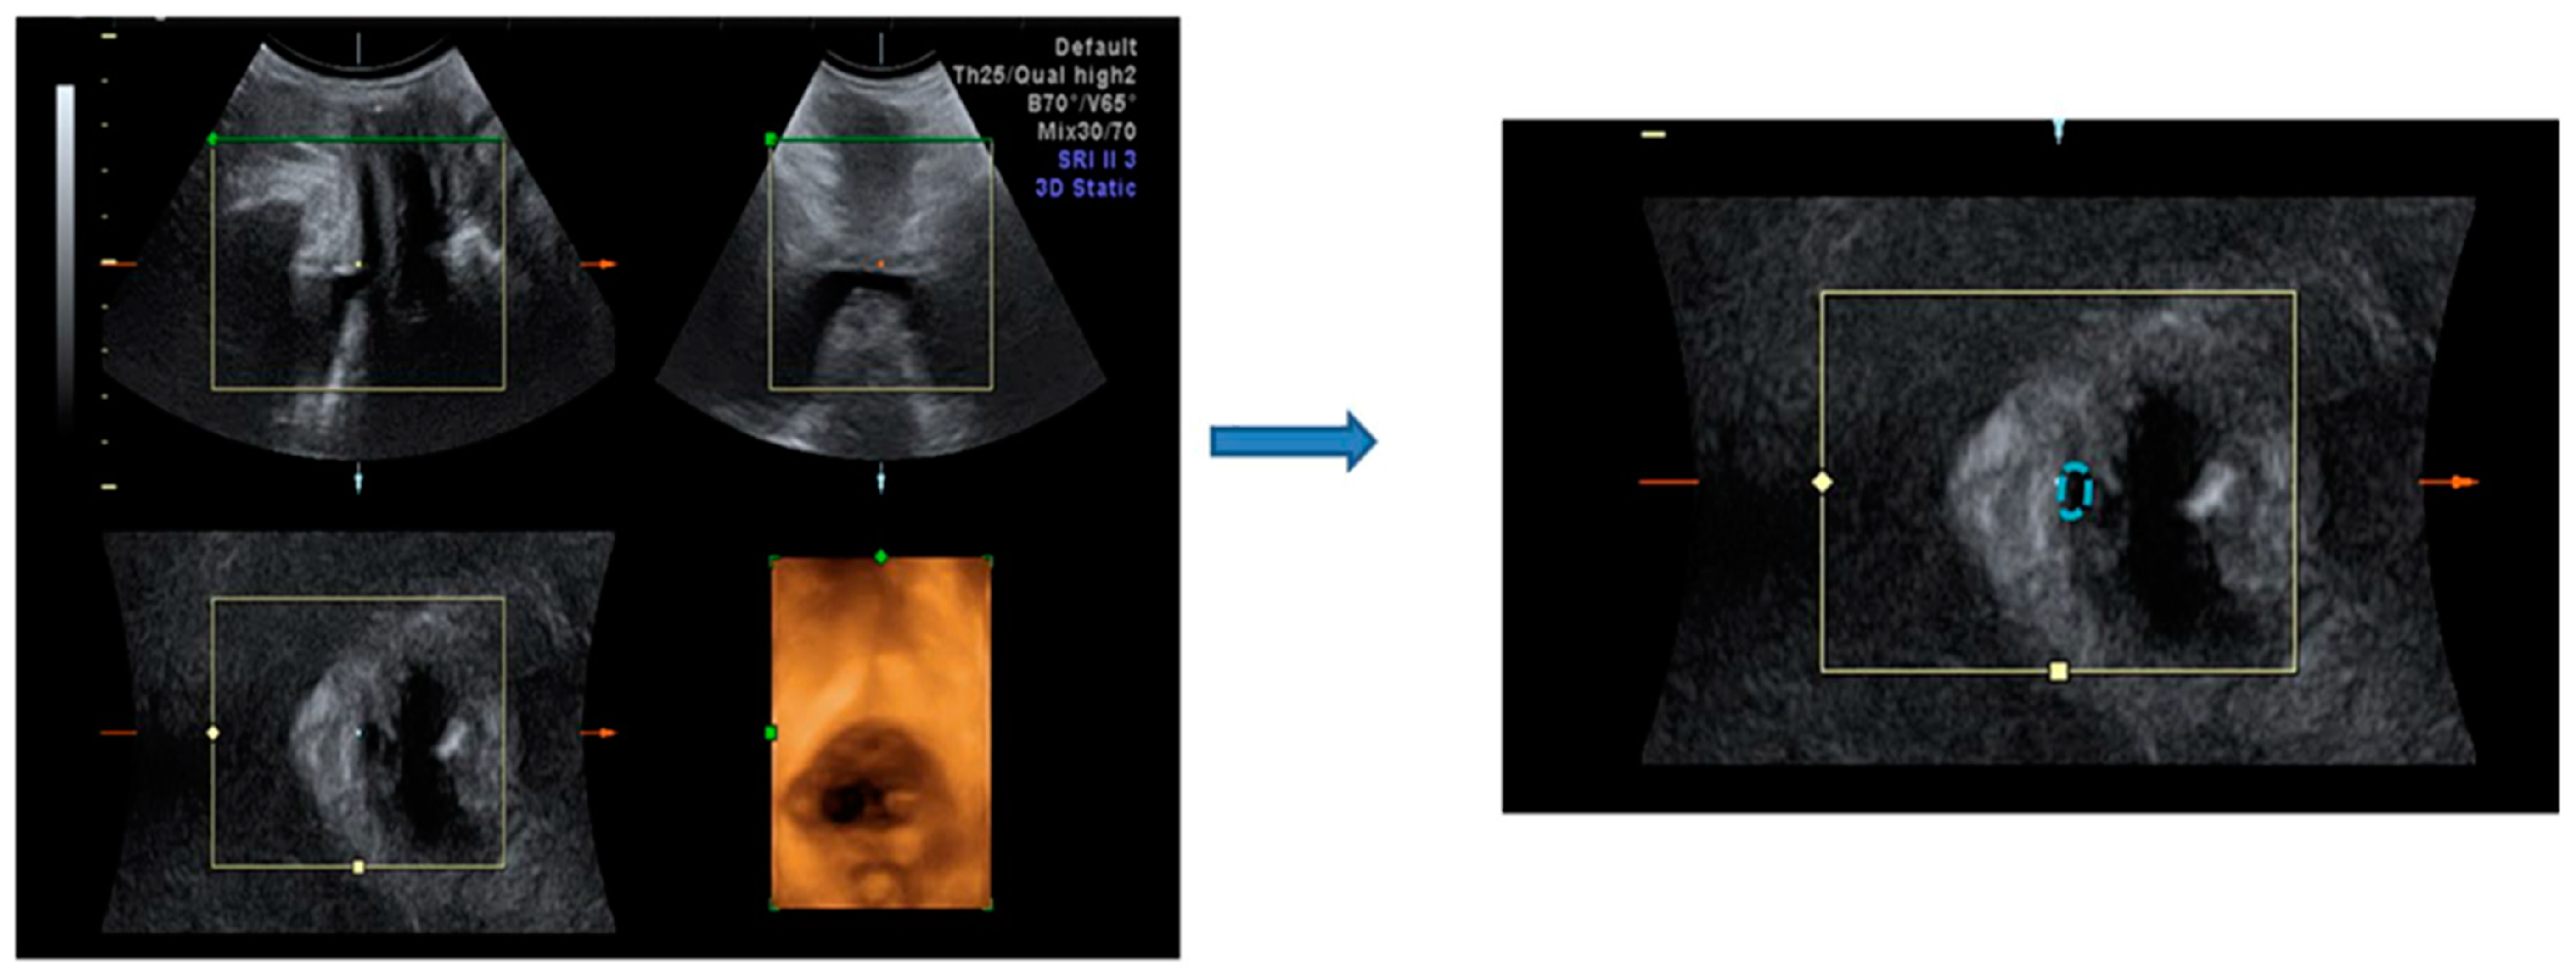

3.4. Effect of HIFEM Treatment on Bladder Neck Mobility in Ultrasound Topography

| n = 14 | Pre-Tx | Post-Tx 6M | p Value | |

|---|---|---|---|---|

| Bladder neck mobility (mm) | 1.2 ± 0.4 | 1.1 ± 0.3 | 0.34 | |

| Urethral area (mm²) | proximal | 0.8 ± 0.4 | 0.7 ± 0.2 | 0.58 |

| Resting | middle | 0.8 ± 0.3 | 0.8 ± 0.2 | 0.17 |

| distal | 2.3 ± 1.0 | 2.5 ± 1.2 | 0.44 | |

| Urethral area (mm²) | proximal | 4.1 ± 1.3 | 5.3 ± 17.2 | 0.34 |

| straining | middle | 0.8 ± 0.2 | 0.8 ± 0.3 | 0.17 |

| distal | 0.7 ± 0.2 | 0.6 ± 0.2 | 0.19 | |

| n = 14 | Rest | Stress | |||||

|---|---|---|---|---|---|---|---|

| Pre-Tx | Post-Tx 6M | p Value | Pre-Tx | Post-Tx 6M | p Value | ||

| Vaginal width | Proximal | 4.6 ± 0.5 | 4.4 ± 0.5 | 0.75 | 4.6 ± 0.5 | 4.4 ± 0.6 | 0.67 |

| Middle | 4.2 ± 0.4 | 4.2 ± 0.5 | 0.44 | 4.4 ± 0.5 | 4.2 ± 0.5 | 0.19 | |

| Distal | 4.3 ± 0.3 | 4.0 ± 0.4 | 0.05 * | 4.4 ± 0.5 | 4.1 ± 0.4 | 0.04 * | |

| Vaginal area | Proximal | 6.1 ± 1.6 | 4.0 ± 1.2 | <0.001 * | 6.9 ± 1.3 | 5.2 ± 2.0 | 0.002 * |

| Middle | 5.6 ± 1.2 | 4.0 ± 1.1 | 0.002 * | 6.5 ± 1.0 | 4.8 ± 1.6 | 0.003 * | |

| Distal | 5.7 ± 1.4 | 4.1 ± 1.1 | 0.001 * | 6.4 ± 1.2 | 4.4 ± 1.3 | <0.001 * | |

| Levator hiatus | Area | 12.0 ± 2.7 | 10.2 ± 2.7 | 0.028 * | 13.5 ± 2.8 | 11.8 ± 3.4 | 0.024 * |

| Short axis | 4.5 ± 0.5 | 4.2 ± 0.5 | 0.104 | 4.7 ± 0.5 | 4.3 ± 0.5 | 0.013 * | |

| Long axis | 3.5 ± 0.6 | 3.4 ± 0.6 | 1.0 | 3.9 ± 0.6 | 3.7 ± 0.6 | 0.5 | |